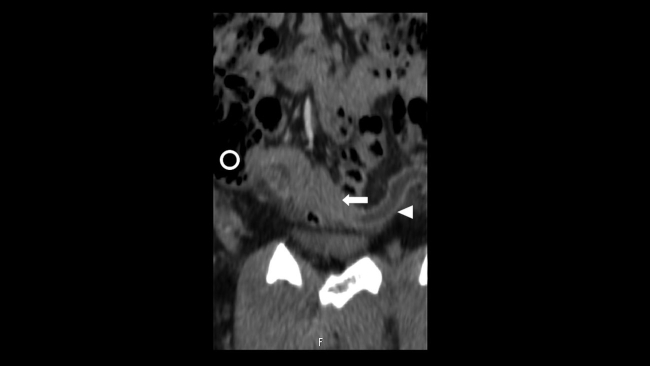

Presentamos el caso de un varón de 30 años que acudió al Servicio de Urgencias de nuestro hospital derivado por su médico de atención primaria, por la presencia de bultomas tumefactos y dolorosos a la palpación, localizados en el cuero cabelludo de un mes de evolución, predominando en zona parietal, temporal y occipital. Asociaba cefalea de características inespecíficas y astenia. Desde hacía dos semanas presentaba nódulos cervicales que impresionaban adenopatías preauriculares, retroauriculares y submandibulares. No presentaba fiebre ni sudoración nocturna. Refería pérdida de 1 a 2 kg en el último mes. Había sido tratado con minociclina 100 mg durante un mes sin mejoría. Durante su estancia, se realizó interconsulta con el Servicio de Dermatología, que completó el estudio con serologías de sífilis, virus de la inmunodeficiencia humana (VIH), hepatitis y citomegalovirus; biopsia de las lesiones de cuero cabelludo, cuyo resultado reveló linfoma / leucemia linfoblástica T; y se practicó punción aspirativa con aguja fina (PAAF) de adenopatía cervical, que confirmó el cuadro linfoide monomorfo. También se solicitó TC toracoabdominopélvica con contraste intravenoso (CIV) que puso de manifiesto: una masa mediastínica anterior que englobaba vasos con leve compresión y desplazamiento sugestiva de conglomerado adenopático y múltiples lesiones focales renales, bilaterales, así como engrosamiento apendicular sugestivos de infiltración linfomatosa (►Figs.1,2a,2b,3a,3b).

En cuanto al linfoma apendicular, es poco frecuente y difícil de sospechar en ausencia de otros hallazgos linfomatosos.4 La etiología más frecuente es por extensión de un linfoma cecal hacia la base apendicular.5 Las manifestaciones clínicas típicas son similares a las de la apendicitis aguda y la TC también es de elección.5 El apéndice puede agrandarse masivamente, pero generalmente mantiene su apariencia.5 El engrosamiento mural difuso tiene atenuación de tejido blando en la TC.4 La tomografía por emisión de positrones (PET) con fluordesoxiglucosa puede demostrar una captación anormal e intensa del radiotrazador en la región del apéndice.6